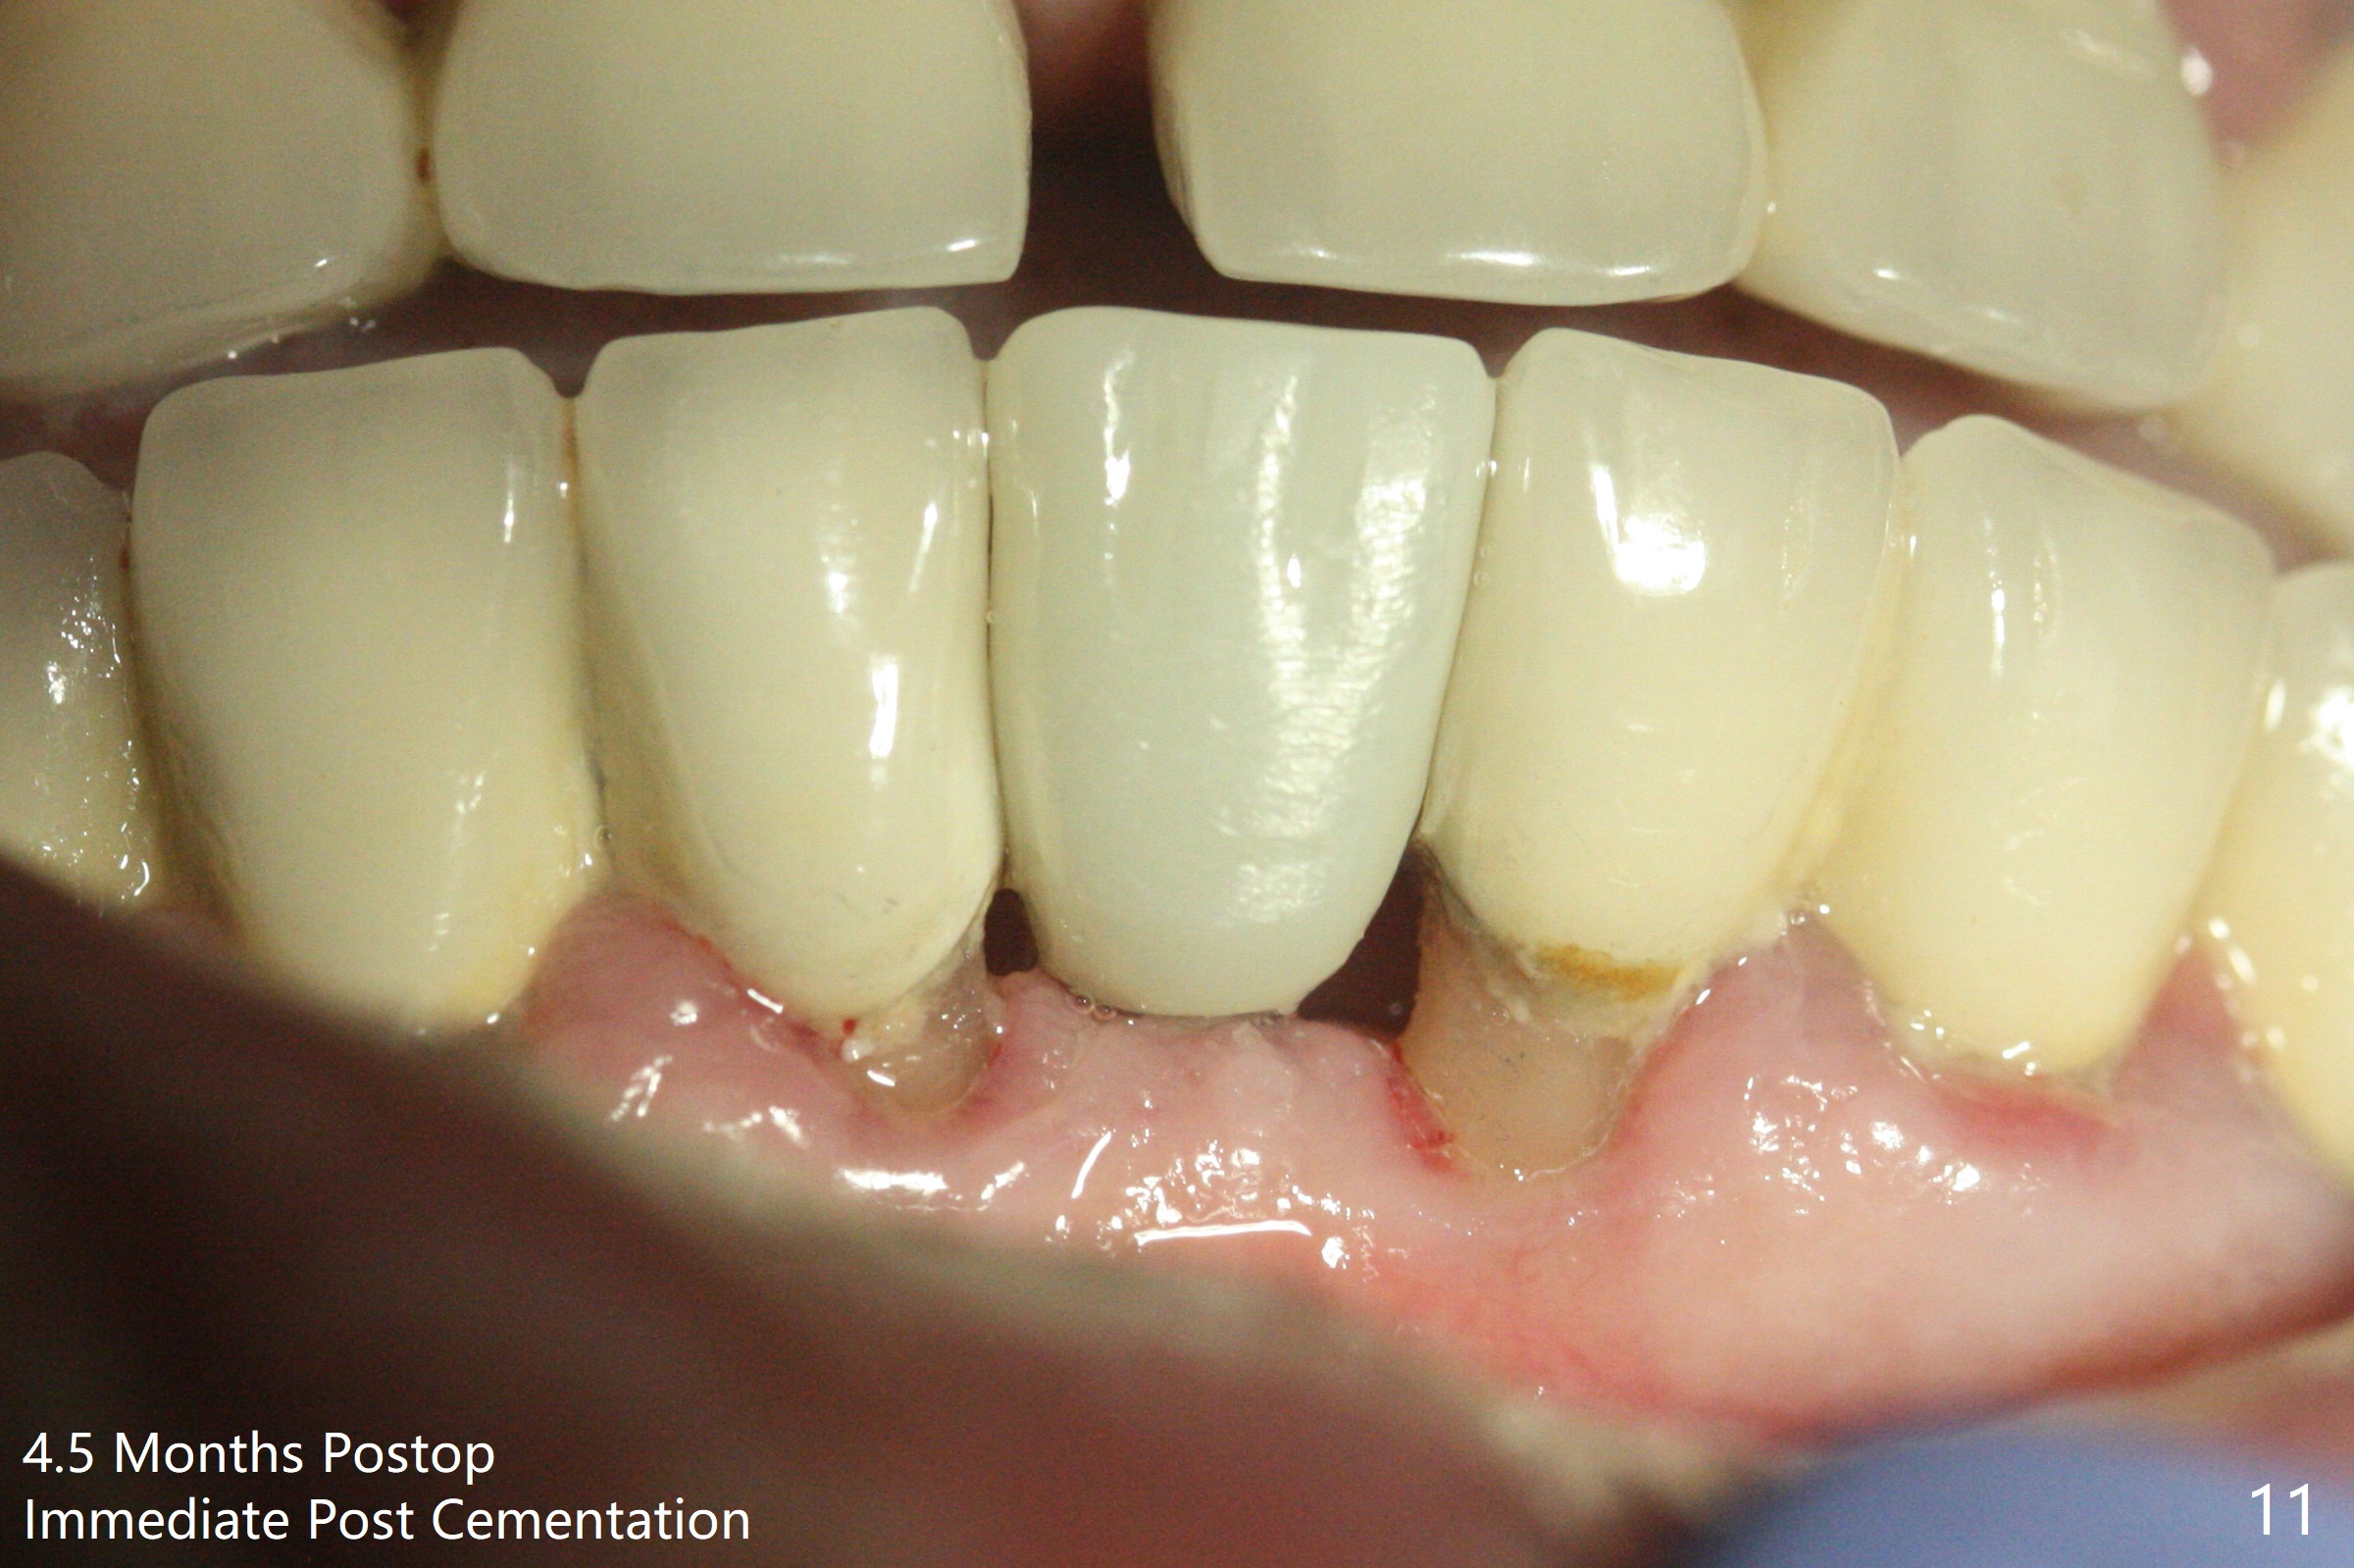

种植前与66岁女病人再次讨论下前牙正中种植可能产生不对称问题,她好像不在乎。术前检查显示下前牙正中间隙偏左(图一),处理似乎容易,但是牙槽嵴相当狭窄(图一 *,二 箭头)。牙槽嵴切除后(大约3 毫米宽(颊舌侧)),初期钻洞似乎偏移右边(图三),矫正后(图四),植入2乘10(4)毫米连体植体(图五,比预计小,因为骨质薄),放置骨粉(图五,六 *)和膜,缝合,制作即刻修复物(图七 T),病人满意,牙槽骨饱满了。术后一个多月临时牙冠取出修正,伤口愈合,由于植骨颊侧没有凹陷(图八),而舌侧隆起(图九:*,与图二术前对比)。其实病人不小心吃牛肉时损伤植体,疼痛几天。尽管最近吃饭时植牙又受伤,但是没有松动,也没有骨质吸收,就是局部结石多(图十,术后四个月)。正式牙冠术后4.5个月粘固(图十一)。